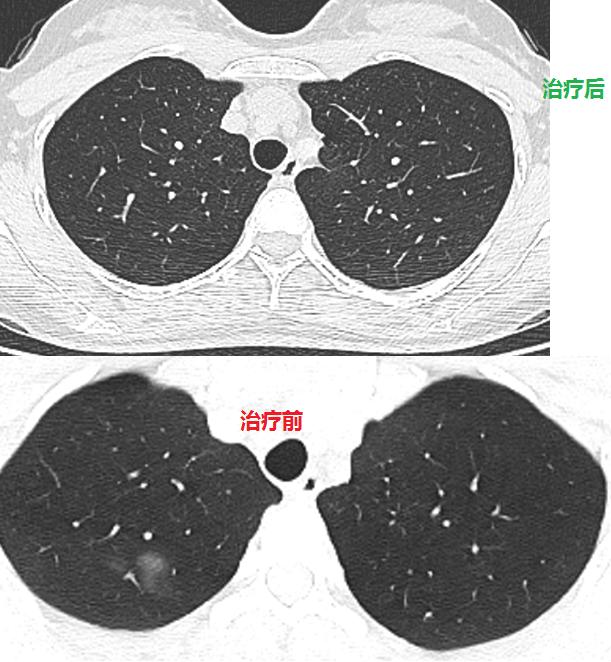

头孢曲松抗感染10天后复查,病灶部分吸收,病情好转出院!

2月后复查,病灶完全吸收!